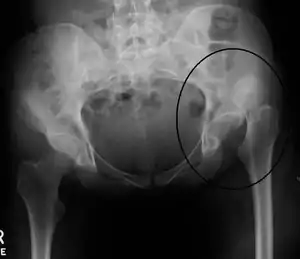

| X-ray showing a joint dislocation of the left hip. | |

Typically, people with hip dislocations present with severe pain and an inability to move the affected leg.[1][4] Diagnosis is made by physical exam and plain X-rays of the hips. A CT scan is recommended following reduction to rule out complications. Complications include osteonecrosis, femoral head fractures, and posttraumatic osteoarthritis.[12][13]

An anterior-posterior (AP) X-ray of the pelvis and a cross-table lateral X-ray[24] of the effected hip are ordered for diagnosis.[4][5][16] The size of the head of the femur is then compared across both sides of the pelvis. The affected femoral head will appear larger if the dislocation is anterior, and smaller if posterior.[7] A CT scan may also be ordered to clarify the fracture pattern.[19]